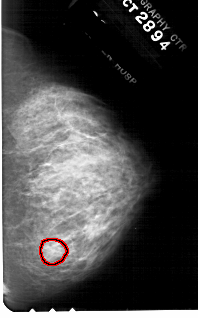

A_1781_1.RIGHT_CC

RIGHT_CC LINES 4756 PIXELS_PER_LINE 2956 BITS_PER_PIXEL 12 RESOLUTION 43.5 OVERLAY

FILE: A_1781_1.RIGHT_CC.OVERLAY

TOTAL_ABNORMALITIES 1

ABNORMALITY 1

LESION_TYPE MASS SHAPE OVAL MARGINS ILL_DEFINED

ASSESSMENT 4

SUBTLETY 3

PATHOLOGY BENIGN

TOTAL_OUTLINES 1

BOUNDARY